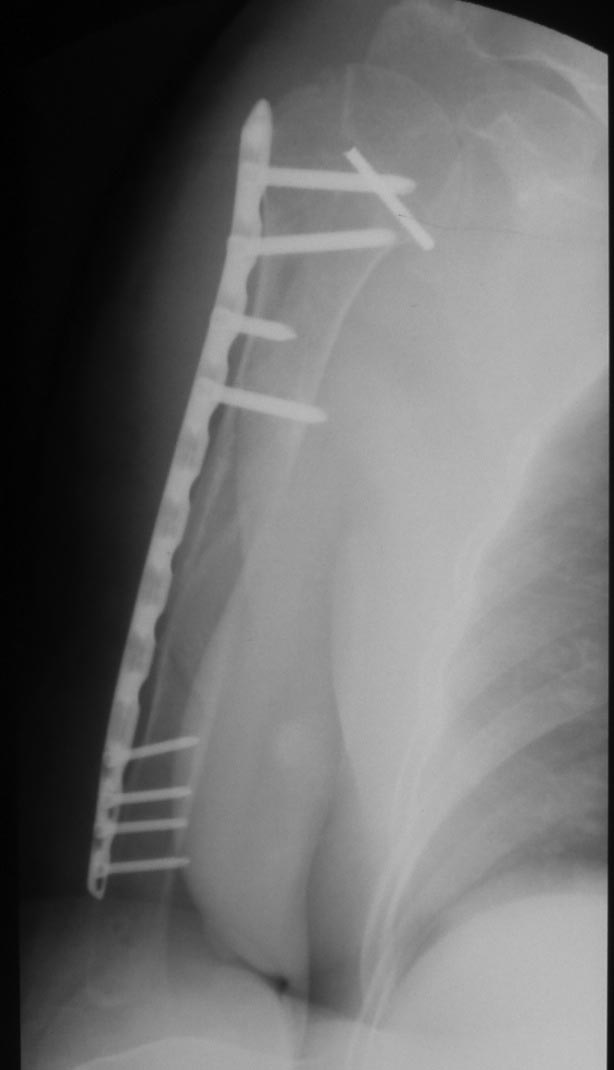

Уважаемые коллеги! Пациент получил травму около 1 года назад, выполнялся остеосинтез по поводу переломов лучевой, бедренной, плечевой костей. Обратился в связи с выраженной контрактурой в коленном суставе (сгибание 10-15 град)и практически отсуствием самостоятельного отведения плеча. Снимки представлены. Планируем выполнить реостеосинтез плеча (скорее всего этим же стержнем, так как другого нет) с коррекцией положения отломков в проксимальном отделе и сближением отломков в области диафиза. По надколеннику пока одна идея - его удаление. Хотелось бы услышать мнение и советы участников форума. - необходима ли будет костная пластика в области диафиза плеча? - адекватен ли по Вашему мнению реостеосинтез стержнем? - какая тактика в отношении ротационной манжеты? - приведет ли удаление надколенника и релиз сустава к существенному улучшению функции? Спасибо.

Надколенник-то, когда сломался? Не при редрессации-ли? Синтез плеча изначально сделан сикось-накось, надо переделывать, стержень - слишком длинный (видно вбили что есть), его использовать не удастся. То место, откуда торчит проксимальный конец стержня с винтами к вращательной манжете отношения не имеет - это немного выше, у бугорков. А что за радикализм в отношении надколенника? Удивляет то, что это пока единственная идея, пришедшая в голову автора;). Надо делать синтез, при этом и осуществить артролиз, а дальше видно будет.

Снимки бы почетче в обеих проекциях увидеть, и на всем протяжении - пока одна мутная проекция, дистального конца ни стержня, ни плечевой кости нет. Функциональные снимки делали, в максимальном отведении? Дефицит отведения только за счет варусной деформации, то есть проксимальный отдел плеча отводится нормально?

Как бы автор вопроса не убеждал себя, что в ситуации с гвоздем (его длиной, расположением относительно манжеты и бугорков и т.д.) все ясно, при таком качестве представленных рентгенограмм в единственной проекции никакой ясности быть не может.

В качестве примера - случай, который оперировал всего 2 недели назад, после похожего остеосинтеза, выполненного год назад. Пациентке 75 лет, тяжелый РА, легла для решения вопроса о ревизии тазобедренного сустава и заодно пожаловалась на то, что рука "крутиться" сама по себе, не поднимается. И болит, конечно. И посмотрите на разницу в информации на снимках головки плеча в двух противоположных проекциях. Даже комментировать ничего не нужно.